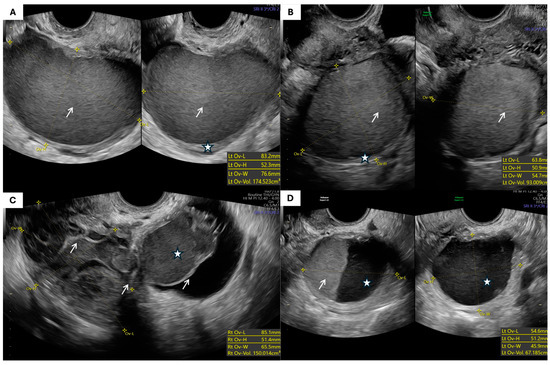

- Morphological Parameters: The morphological assessment included the largest tumor diameter, volume (calculated using the prolate ellipsoid formula: length × height × width × 0.523), laterality, capsule thickness, and internal echogenicity (categorized as anechoic, homogeneous low-level “ground-glass”, hyperechoic, or mixed/heterogeneous). The presence of septa, papillary projections, solid components, acoustic shadowing, free fluid in the pouch of Douglas, and signs of tumor fixation were also recorded.

| Morphological Type (IOTA Terminology) | Endometriomas (n = 55) | % | Teratomas (n = 49) | % | p-Value |

|---|---|---|---|---|---|

| Unilocular cyst with ground-glass echogenicity | 25 | 45.5% | 0 | 0% | <0.001 * |

| Unilocular solid cyst with hyperechoic content | 1 | 1.8% | 10 | 20.4% | |

| Multilocular cyst | 8 | 14.5% | 5 | 10.2% | |

| Multilocular solid cyst | 9 | 16.4% | 25 | 51.0% | |

| Cyst with papillary projections (unilocular or bilocular) | 1 | 1.8% | 1 | 2.0% | |

| Solid tumor | 3 | 5.5% | 4 | 8.2% | |

| Other/not otherwise specified | 8 | 14.5% | 4 | 8.2% |